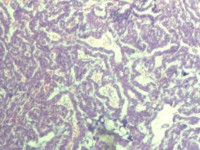

性别

女

年龄

55岁

临床诊断

异常子宫出血

一般病史

阴道不规则出血1月

标本名称

子宫内膜

大体所见

灰白色组织1堆、4*3.4*2.2CM大。

能诊断癌吗

子宫内膜样腺癌